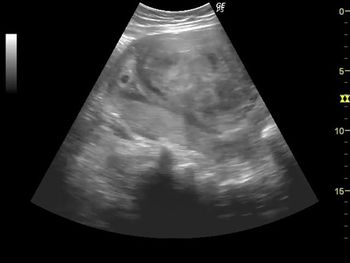

Challenge your diagnostic skills. What's your diagnosis based on these fetal abdominal images?

Challenge your diagnostic skills. What's your diagnosis based on these abdominal images of a late second trimester fetus?